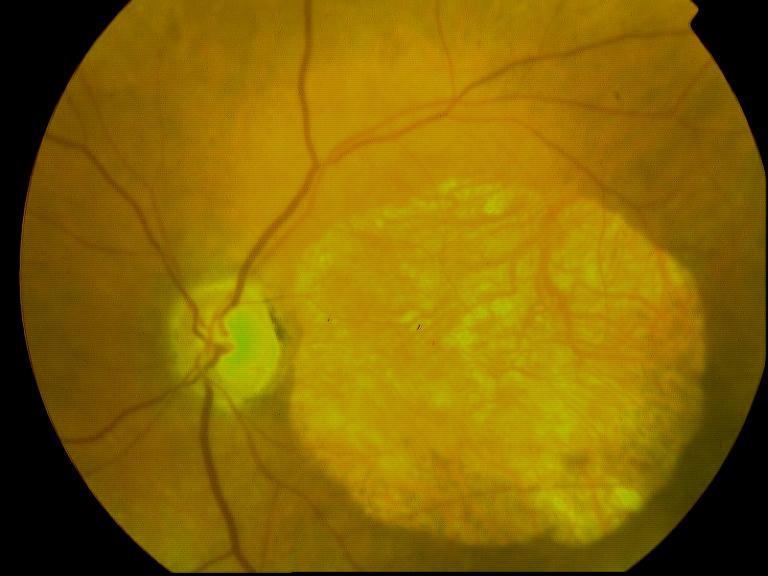

CICATRICE APRES EXERESE CHIRURGICALE DE NEOVAISSEAUX

IM000014.jpg